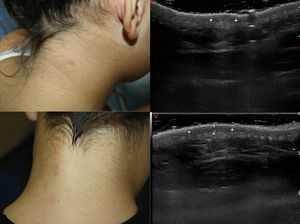

Clínicamente se suelen presentar como una placa o un nódulo «solitarios», pueden ser múltiples, mal definidos, con un leve eritema o hiperpigmentación, y suelen ser asintomáticos aunque pueden ocasionar un prurito leve. En la forma pediátrica las lesiones predominan en la región cervical (56%) y tienen una tendencia a la remisión espontánea3. La forma del adulto, sin embargo, suele localizarse en los hombros o en la parte proximal de los miembros. Es más frecuente en mujeres (96%) y no tiene tendencia a la remisión espontánea4. El diagnóstico diferencial clínico es muy amplio4 (fig. 1).

Los datos clínicos se resumen en la tabla 1. Se incluyeron 3 mujeres y 5 varones. La edad al diagnóstico osciló entre los 20 meses y los 15 años. Las lesiones se localizaban en el cuello (6 pacientes), en el hombro izquierdo (un paciente) y en la región occipital (un paciente). El tiempo de evolución de las lesiones fue de entre un mes y un año antes de consultar por ellas. Clínicamente se trataba de lesiones nodulares o en placa, mal delimitadas en 6 de los pacientes (en 2 casos estaban bien delimitadas), levemente eritematosas o hiperpigmentadas. Uno de los pacientes presentaba 2 lesiones. Tres de las lesiones eran dolorosas y 2 eran pruriginosas; el resto eran asintomáticas.

La ecografía con sonda de alta resolución (Esaote MyLab® Class C, sonda lineal de 18MHz) mostró unas lesiones redondeadas dermohipodérmicas hipoecoicas mal definidas, no encapsuladas, sin flujo doppler, excepto en 2 casos, que presentaban flujo doppler en la periferia.